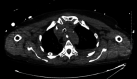

A 73-year-old female underwent open mitral valve replacement with transesophageal echocardiography (TEE) guidance. She developed upper gastrointestinal bleeding postoperatively and was found on upper endoscopy to have a bleeding site at the gastric cardia with the appearance of focal trauma and a possible puncture site. A submucosal bluish protrusion was seen throughout the esophagus with a mucosal flap at the proximal esophagus. As a unifying diagnosis, it was suspected that the intraoperative TEE probe caused a submucosal dissection with point of entry at the proximal esophagus, running the entire length of the esophagus and exiting at the gastric cardia, giving rise to a clinical upper gastrointestinal bleed. Closure of the esophageal defect was achieved using an endoclip. A CT scan showed focal pneumomediastinum along the proximal esophagus, confirming the hypothesis. We report the first case to our knowledge of iatrogenic pan-esophageal submucosal dissection, which, in this case, presented as a clinical bleed from the exit point trauma to the gastric cardia mucosa caused by a TEE probe. Endoscopic management of the gastric injury as well as the esophageal defect led to resolution of the bleeding and avoidance of mediastinitis, respectively, allowing for an excellent recovery.